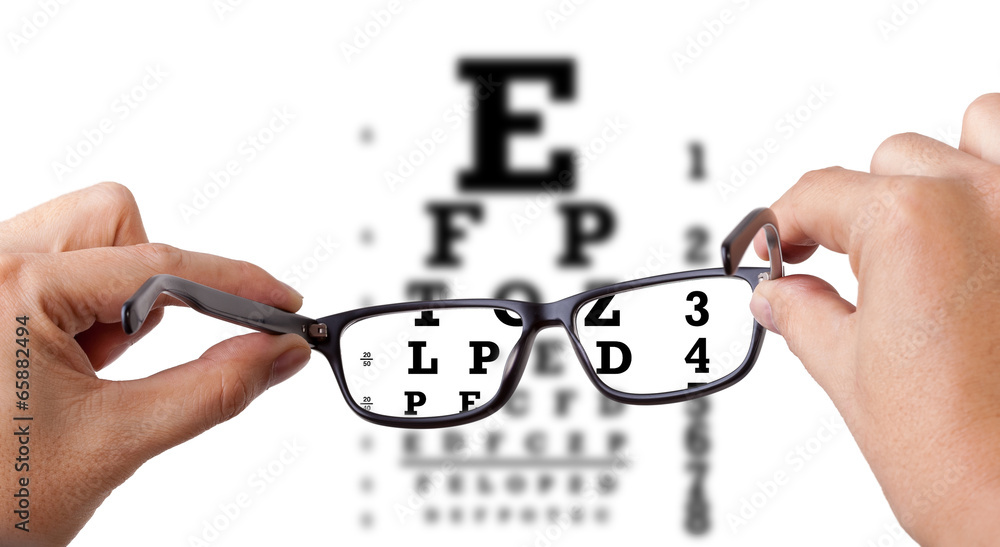

Our eye care specialist examine, diagnose and treat injuries and health conditions that affect your eyes and vision. Our services include eye testing and prescriptions of eyeglasses, contact lenses,and other vision aids, and medications for certain eye conditions.